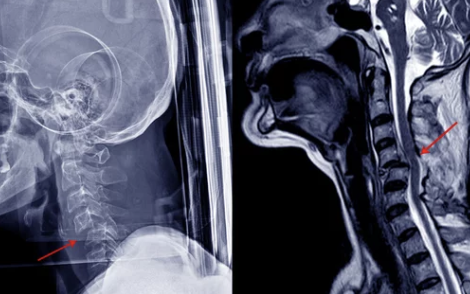

4. 목디스크 진단과 치료법: 비수술적 치료부터 수술까지

목디스크가 의심되면 정확한 진단을 통해 치료 방법을 결정해야 해요. 요즘은 비수술적 치료법이 많이 발달해 있어 초기에는 수술 없이 치료가 가능해요.